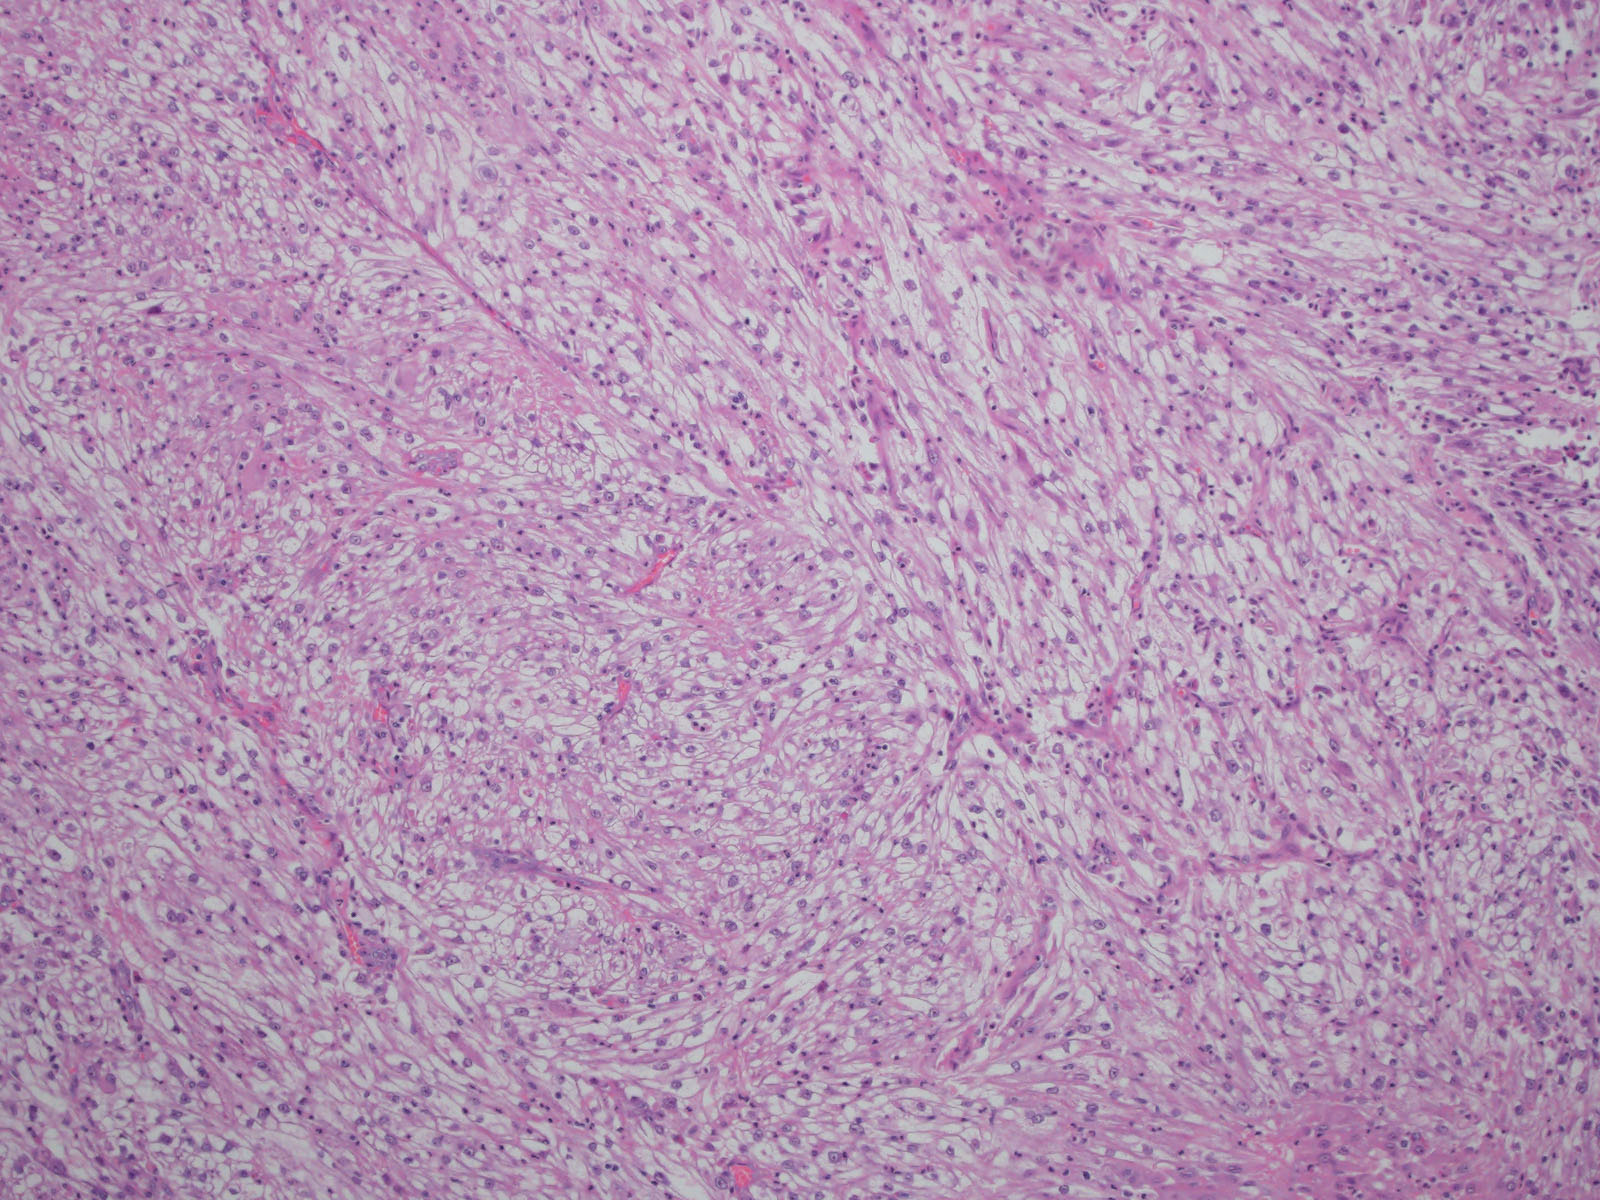

Consensus grade: Clear cell RCC

Show diagnosis by expert panel members| User | Diagnosis | Difficulty | Comment |

|---|---|---|---|

| Pathologist 1 | Clear cell RCC | Typical | |

| Pathologist 2 | Clear cell RCC | Typical | |

| Pathologist 3 | Renal cell carcinoma, unclassified | Not typical |

Could be a clear cell but not sure |

| Pathologist 4 | Clear cell RCC | Not typical | |

| Pathologist 5 | Clear cell RCC | Typical |

with sarcomatoid differentiation |

| Pathologist 6 | Clear cell RCC | Typical | |

| Pathologist 7 | Clear cell RCC | Typical |

sarcomatoid |

| Pathologist 8 | Clear cell RCC | Typical |

| Pathologist 9 | Insufficient tumor for diagnosis | Not typical | |

| Pathologist 10 | Clear cell RCC | Typical | |

| Pathologist 11 | Clear cell RCC | Not typical | |

| Pathologist 12 | Clear cell RCC | Not typical | |

| Pathologist 13 | Clear cell RCC | Not typical | |

| Pathologist 14 | Clear cell RCC | Not typical | |

| Pathologist 15 | Clear cell RCC | Typical | |

| Pathologist 16 | Clear cell RCC | Typical | |

| Pathologist 17 | Clear cell RCC | Not typical | |

| Pathologist 18 | Clear cell RCC | Not typical |